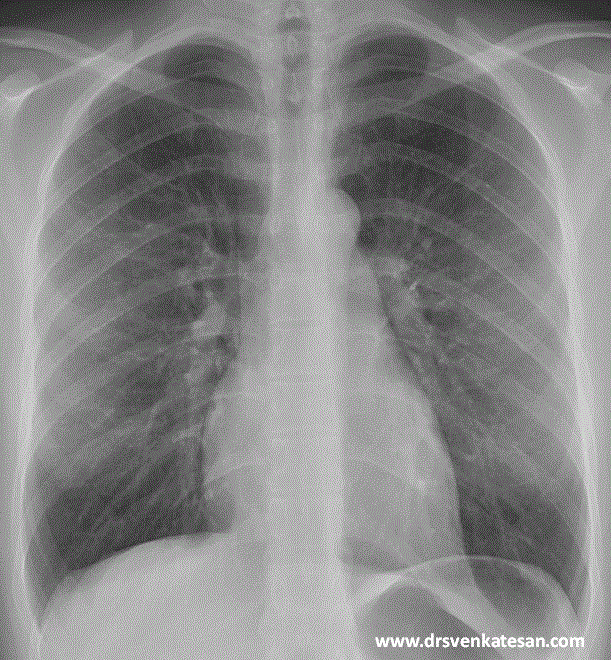

Since I have struggled with X ray orientation of heart chambers in my early days (Still i do sometimes!) Just thought , why we are not fusing a X-ray with a given patients echocardiogram that will help understand the chamber anatomy .

Fusion Image of X ray chest PA view with apical 4 chamber in ECHO. (Rotated to specified angle to match heart border)

Note : The Left atrium is not only left of RA , its also posterior and superior to RA.This makes the IAS not actually pure right left to relationship but also a slight infero to superior and antero posterior orientation.(This can be realised when we puncture the IAS from RA side the needle goes more of superior)